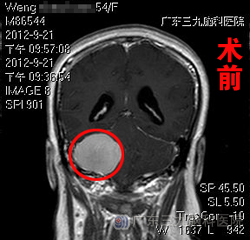

相关头部检查提示:右侧桥小脑角区占位性病变,考虑为脑膜瘤(肿瘤较大,约为46.3mm×33.6mm×39.3mm);幕上梗阻性脑积水。在明确手术指证,完善术前检查后,9月25日,由神经外七科吾太华主任主刀,翁老师在全麻下接受了右侧侧脑室外引流术+右侧桥小脑角区占位切除术。